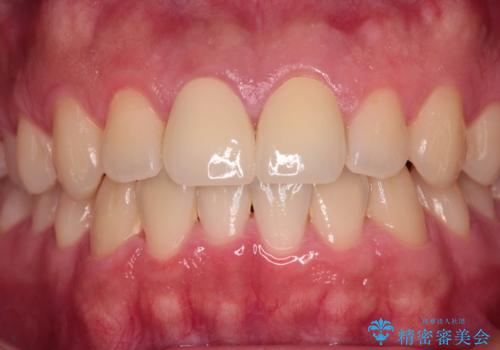

幸いにも神経組織に影響はなく、健全な状態で治療を終えることができました。

歯肉の腫脹が目立っていたため、衛生指導も並行して行い、引き締まった歯肉になりました。

外傷歯は、将来的に歯根吸収を起こす可能性があるため、定期的なレントゲン撮影により経過観察が必要となります。